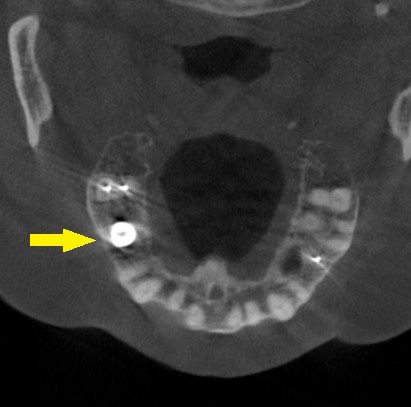

これならと同意いただけましたので、本日、直径6mm、長さ7mmのインプラントを人工骨を用いることなく埋入しました。

下の写真、2段目が手術前、3段目が手術後のCTです。